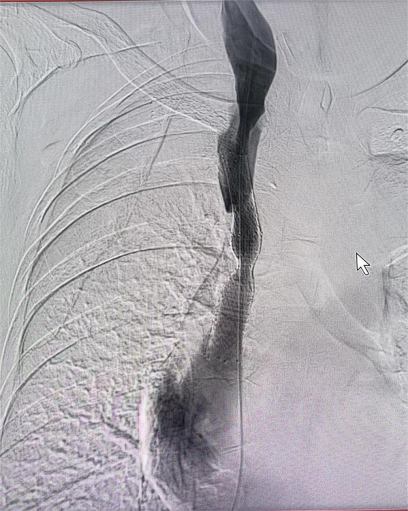

图片

术中造影证实上腔静脉闭塞